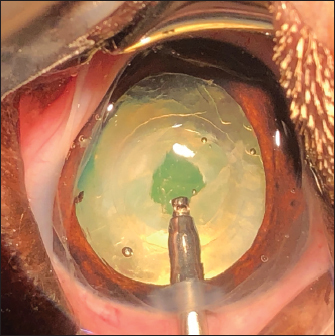

Fig. 4. APC performed in the space between the IOL optic and the PC. Cutting of the PC to the right (a), then to the left (b). Removal of the central capsular opacity with the Utrata forceps (c).

The APC was initiated by very gently making small perforations of the PC with a 30-gauge needle. Then, long curved Vannas scissors were inserted through this narrow posterior capsulotomy to cut PC to the right, removed from the eye, and then reintroduced for a cut to the left (Fig. 4). APC was then performed continuously with Utrata forceps, from one flap to the other to obtain a circular axial opening of about 3 mm diameter (Fig. 4). A slight anterior vitrectomy (Anterior Vitrectomy Probe w/21 GA Infusion Cannula, Alcon Laboratories, Inc. Fort Worth, USA) was then performed through the PC opening (under the IOL when initially placed) to prevent a possible vitreous presentation (Fig. 5). Using the irrigation/aspiration handpiece, IOL was the centered in the bag and viscoelastic removed. As mentioned above and depending on the case, the instruments (needle, Vannas scissors, Utrata forceps, vitreotome) were manipulated either with direct access to the PC thanks to the lateral positioning of IOL inside the capsular bag or in the space between the IOL optic and PC. The corneal wound was sutured by separate Polyglactin 910 absorbable stitches (Vicryl 9-0, Ethicon, Puerto Rico, USA). Administration of intracameral 25 mcg of tissue plasminogen activator (Actilyse, Boehringer, France) and 0.5 ml of 0.01% carbachol (Carbachol Intraocular Solution USP, Freedom Ophthalmic Pvt Inc, NY, USA) were achieved immediately after corneal incision closure in all cases. Methylprednisolone acetate (Depomedrol, Zoetis, Malakoff, France) was injected subconjunctivally at a dose of 5 mg in all cases, with no dog being diabetic.